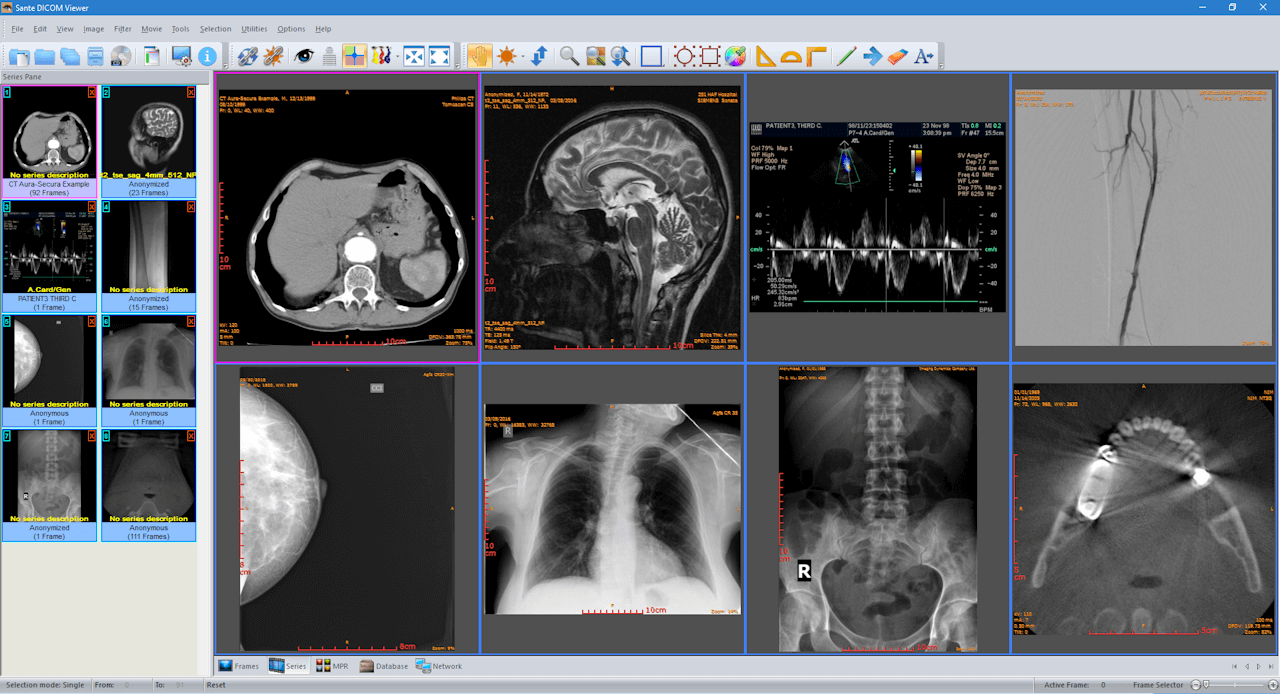

The RadiAnt DICOM image viewer is a simple, fast platform that is compatible with Windows. It offers multiple features, including MPR, MIP, and image fusion. Images can be exported to JPEG, PNG, and other image formats. They can also be copy-pasted directly to presentations and word documents.

The application is just a viewer and does not offer storage space. Their website has a disclaimer explicitly stating that they do not have any certifications, and as such, the product is not intended for diagnostic use. However, it is handy for students and residents for studying medical images and research purposes.